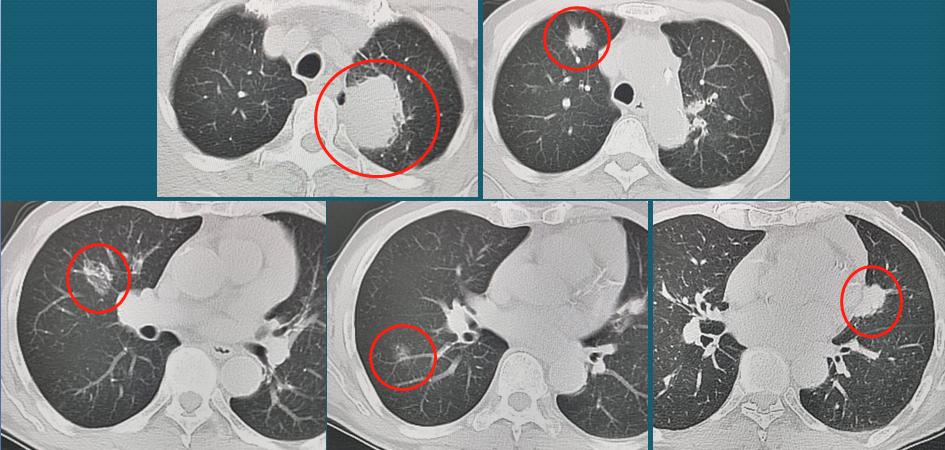

下图是一位70岁老人,不知什么原因被癌细胞盯上了,双肺总共长了5个肺癌,实性、混磨、纯磨的都有:

双肺多原发肺癌

图片中1、5号病灶为实性结节,2号病灶为混合磨玻璃结节,3号病灶为囊腔样肺癌,4号病灶为纯磨玻璃结节。

这位病人很不幸,长了5个教科书式的肺癌病灶,其中最可怕的是1号、5号病灶,表现为不规则的实性肺结节,贴近胸膜,比较容易沿着胸膜丰富的脉管系统(主要是淋巴管)发生早期转移扩散。而磨玻璃结节多为惰性病灶,囊腔样肺癌及时发现,手术效果也很好。

事实上,老人也的确是已经发生颈部淋巴结转移,失去手术机会了。